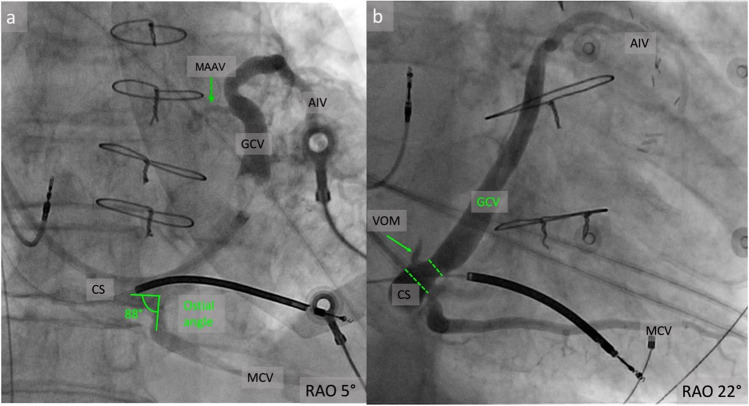

Purpose of review: This review aims to synthesize current knowledge on the angiographic anatomy of the coronary sinus and its tributaries veins, with focus on venous branches other than classical ones used in cardiac resynchronization therapy. It also presents common anatomical aspects that could impact the clinical outcome.

Recent findings: Recent advancements in the electrophysiology field, like epicardial arrhythmia mapping and ablation through coronary sinus or cardiac pacing from atypical veins requires a detailed angiographic assessment of cardiac veins. There is an increased interest for the veins coursing in the left ventricular summit (LVS) area and could potentially provide a pathway to reach the LVS arrhythmogenic foci. However, there is no consensus regarding the nomenclature and classification of these veins. This review could offer a better understanding of the coronary sinus and its tributary veins distribution, dimensions and relationship with nearby structures that could help the development of new ablation and pacing tools and strategies, with higher success rates.